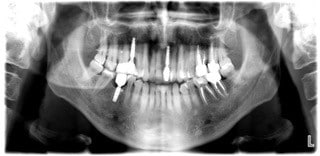

Podczas pierwszej wizyty w Prodent Gdańsk przeprowadzony został z pacjentem wywiad medyczny, wykonane zostały zdjęcia wewnątrzustne i badania rentgenowskie wraz z tomografią komputerową. Pan Marcin miał też możliwość przedstawić nam swoje oczekiwania. Pacjent został umówiony na higienizację, a doktor Ewa Odya-Bojanowska jako lekarz koordynujący wykonała kompleksowy plan leczenia w oparciu o przeprowadzone wcześniej badania rentgenowskie, przegląd stanu jamy ustnej i zębów oraz badania łukiem dynamicznym Gerbera. Zaplanowano kompleksowe leczenie w centralnej relacji, wyrównanie płaszczyzny zgryzu, zbilansowane kontakty okluzyjne zabezpieczające pacjenta przed wieloma problemami przyszłości.

Leczenie przewidywało następujące procedury: